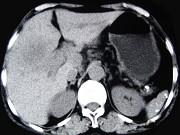

问题 女,65岁,右季肋区疼痛二个月,CT扫描所见如图,最可能的诊断是()

选项 A.慢性胆囊炎 B.胆囊癌腹膜后淋巴结转移 C.胆管细胞癌 D.胆囊黄色肉芽肿 E.胆囊腺肌增生症

答案 B